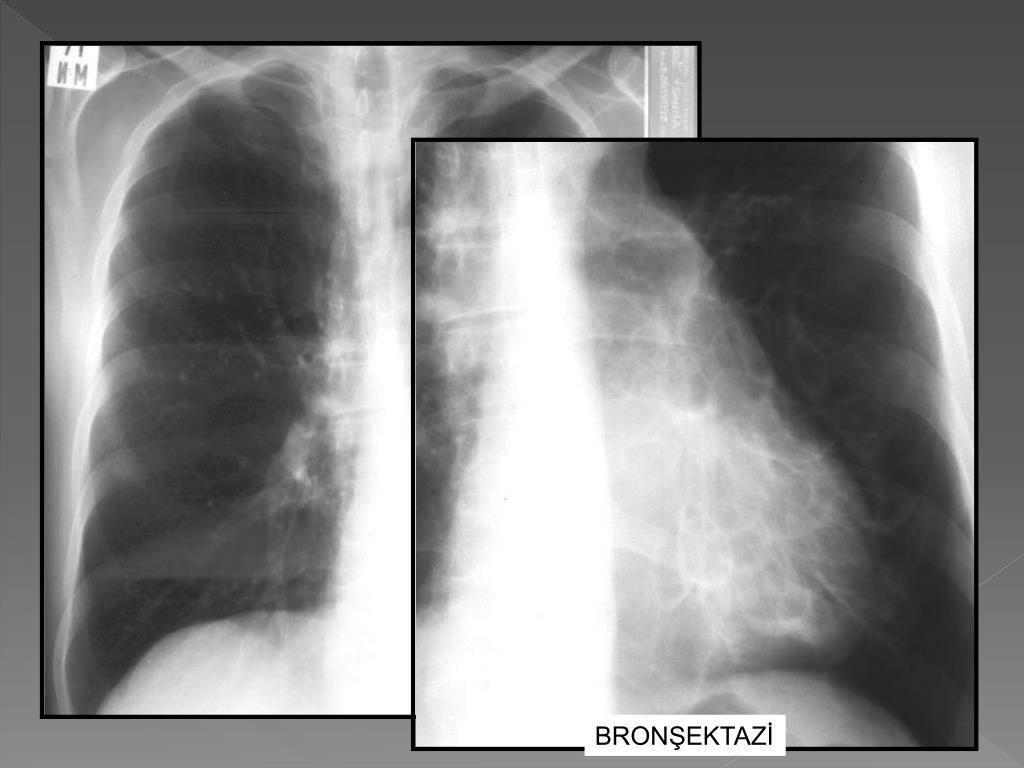

19. AKCİĞER KANSERİ

27. BRONŞEKTAZİ